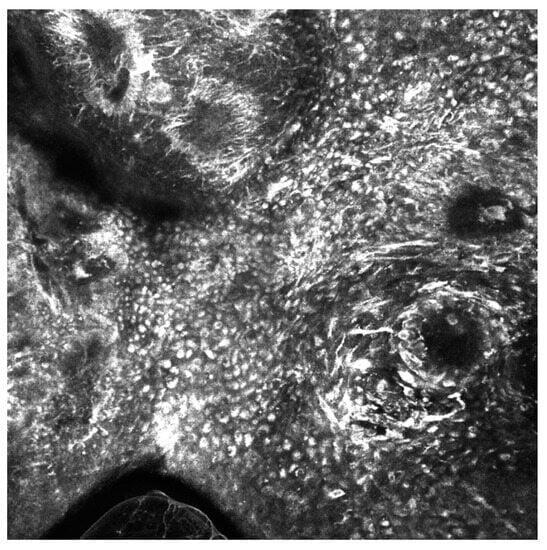

3.2. Artificial Intelligence-Based Approaches to Analysis of Reflectance Confocal Microscopy (RCM) Images

- Wodzinski, M.; Skalski, A.; Witkowski, A.; Pellacani, G.; Ludzik, J. Convolutional Neural Network Approach to Classify Skin Lesions Using Reflectance Confocal Microscopy. Annu. Int. Conf. IEEE Eng. Med. Biol. Soc. 2019, 2019, 4754–4757. [Google Scholar] [CrossRef]

- D’alonzo, M.; Bozkurt, A.; Alessi-Fox, C.; Gill, M.; Brooks, D.H.; Rajadhyaksha, M.; Kose, K.; Dy, J.G. Semantic segmentation of reflectance confocal microscopy mosaics of pigmented lesions using weak labels. Sci. Rep. 2021, 11, 3679. [Google Scholar] [CrossRef]

| Convolutional Neural Network Approach to Classify Skin Lesions Using Reflectance Confocal Microscopy | Wodzinski et al. [49] | CNN-based approach to classify skin lesions using the reflectance confocal microscopy (RCM) mosaics | CNN | 429 RCM mosaics | Test set classification accuracy = 87% |

| Semantic segmentation of reflectance confocal microscopy mosaics of pigmented lesions using weak labels | D’Alonzo et al. [50] | Development of a weakly supervised machine learning model to perform semantic segmentation of architectural patterns encountered in RCM mosaics | Deep Learning | 157 RCM mosaics | Trained DNN achieved an average AUC of 0.969; Dice coefficient = 0.778 |